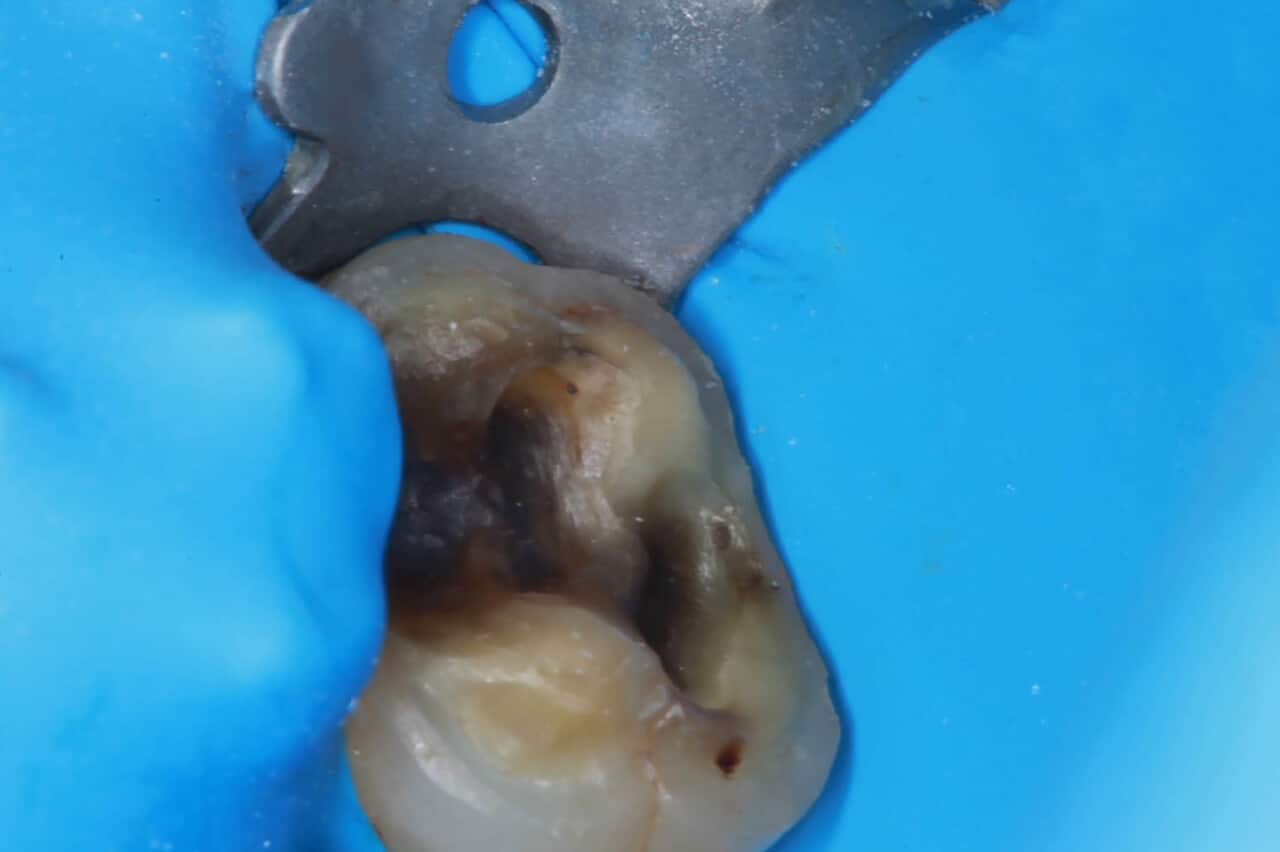

Légende : Fig.1a, 1b : État initial de la 16 et de la 26.

On observe l’état initial de la 16 et de la 26 (Fig.1a, b), elles présentent une reconstruction ancienne par amalgame dentaire corrodé, avec percolation bactérienne importante, des signes de micro-fissures amélaires, une altération amélaire périphérique et une plage d’hypominéralisation allant de la face palatine à la zone sous obturation coronaire.

Préparation et dépose de l’ancienne restauration (Fig.2, 3)

Dans le respect des concepts minimalement invasifs et biomimétiques, on réalise tout d’abord la dépose des anciennes restaurations à l’amalgame. Un nettoyage méticuleux de la zone dentinaire sous l’obturation est réalisé, car la difficulté est que les tissus ont été colorés par les ions métalliques issus de l’amalgame dentaire. On parle de tatouage dentinaire. Cette dyschromie acquise iatrogène pose un problème dans l’exérèse d’éventuelles lésions carieuses sous restauration d’autant que la dent présente déjà à l’origine une hypominéralisation amélaire et dentinaire devant être discriminée d’une lésion carieuse active.